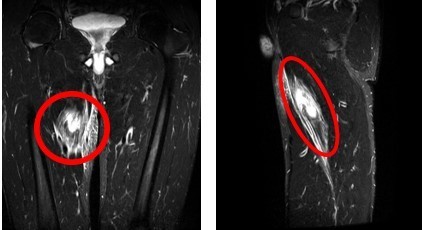

画像所見:MRI検査で内転筋の損傷を確認しました。(〇で囲んだ部分)

(正面から見た場合) (横から見た場合)